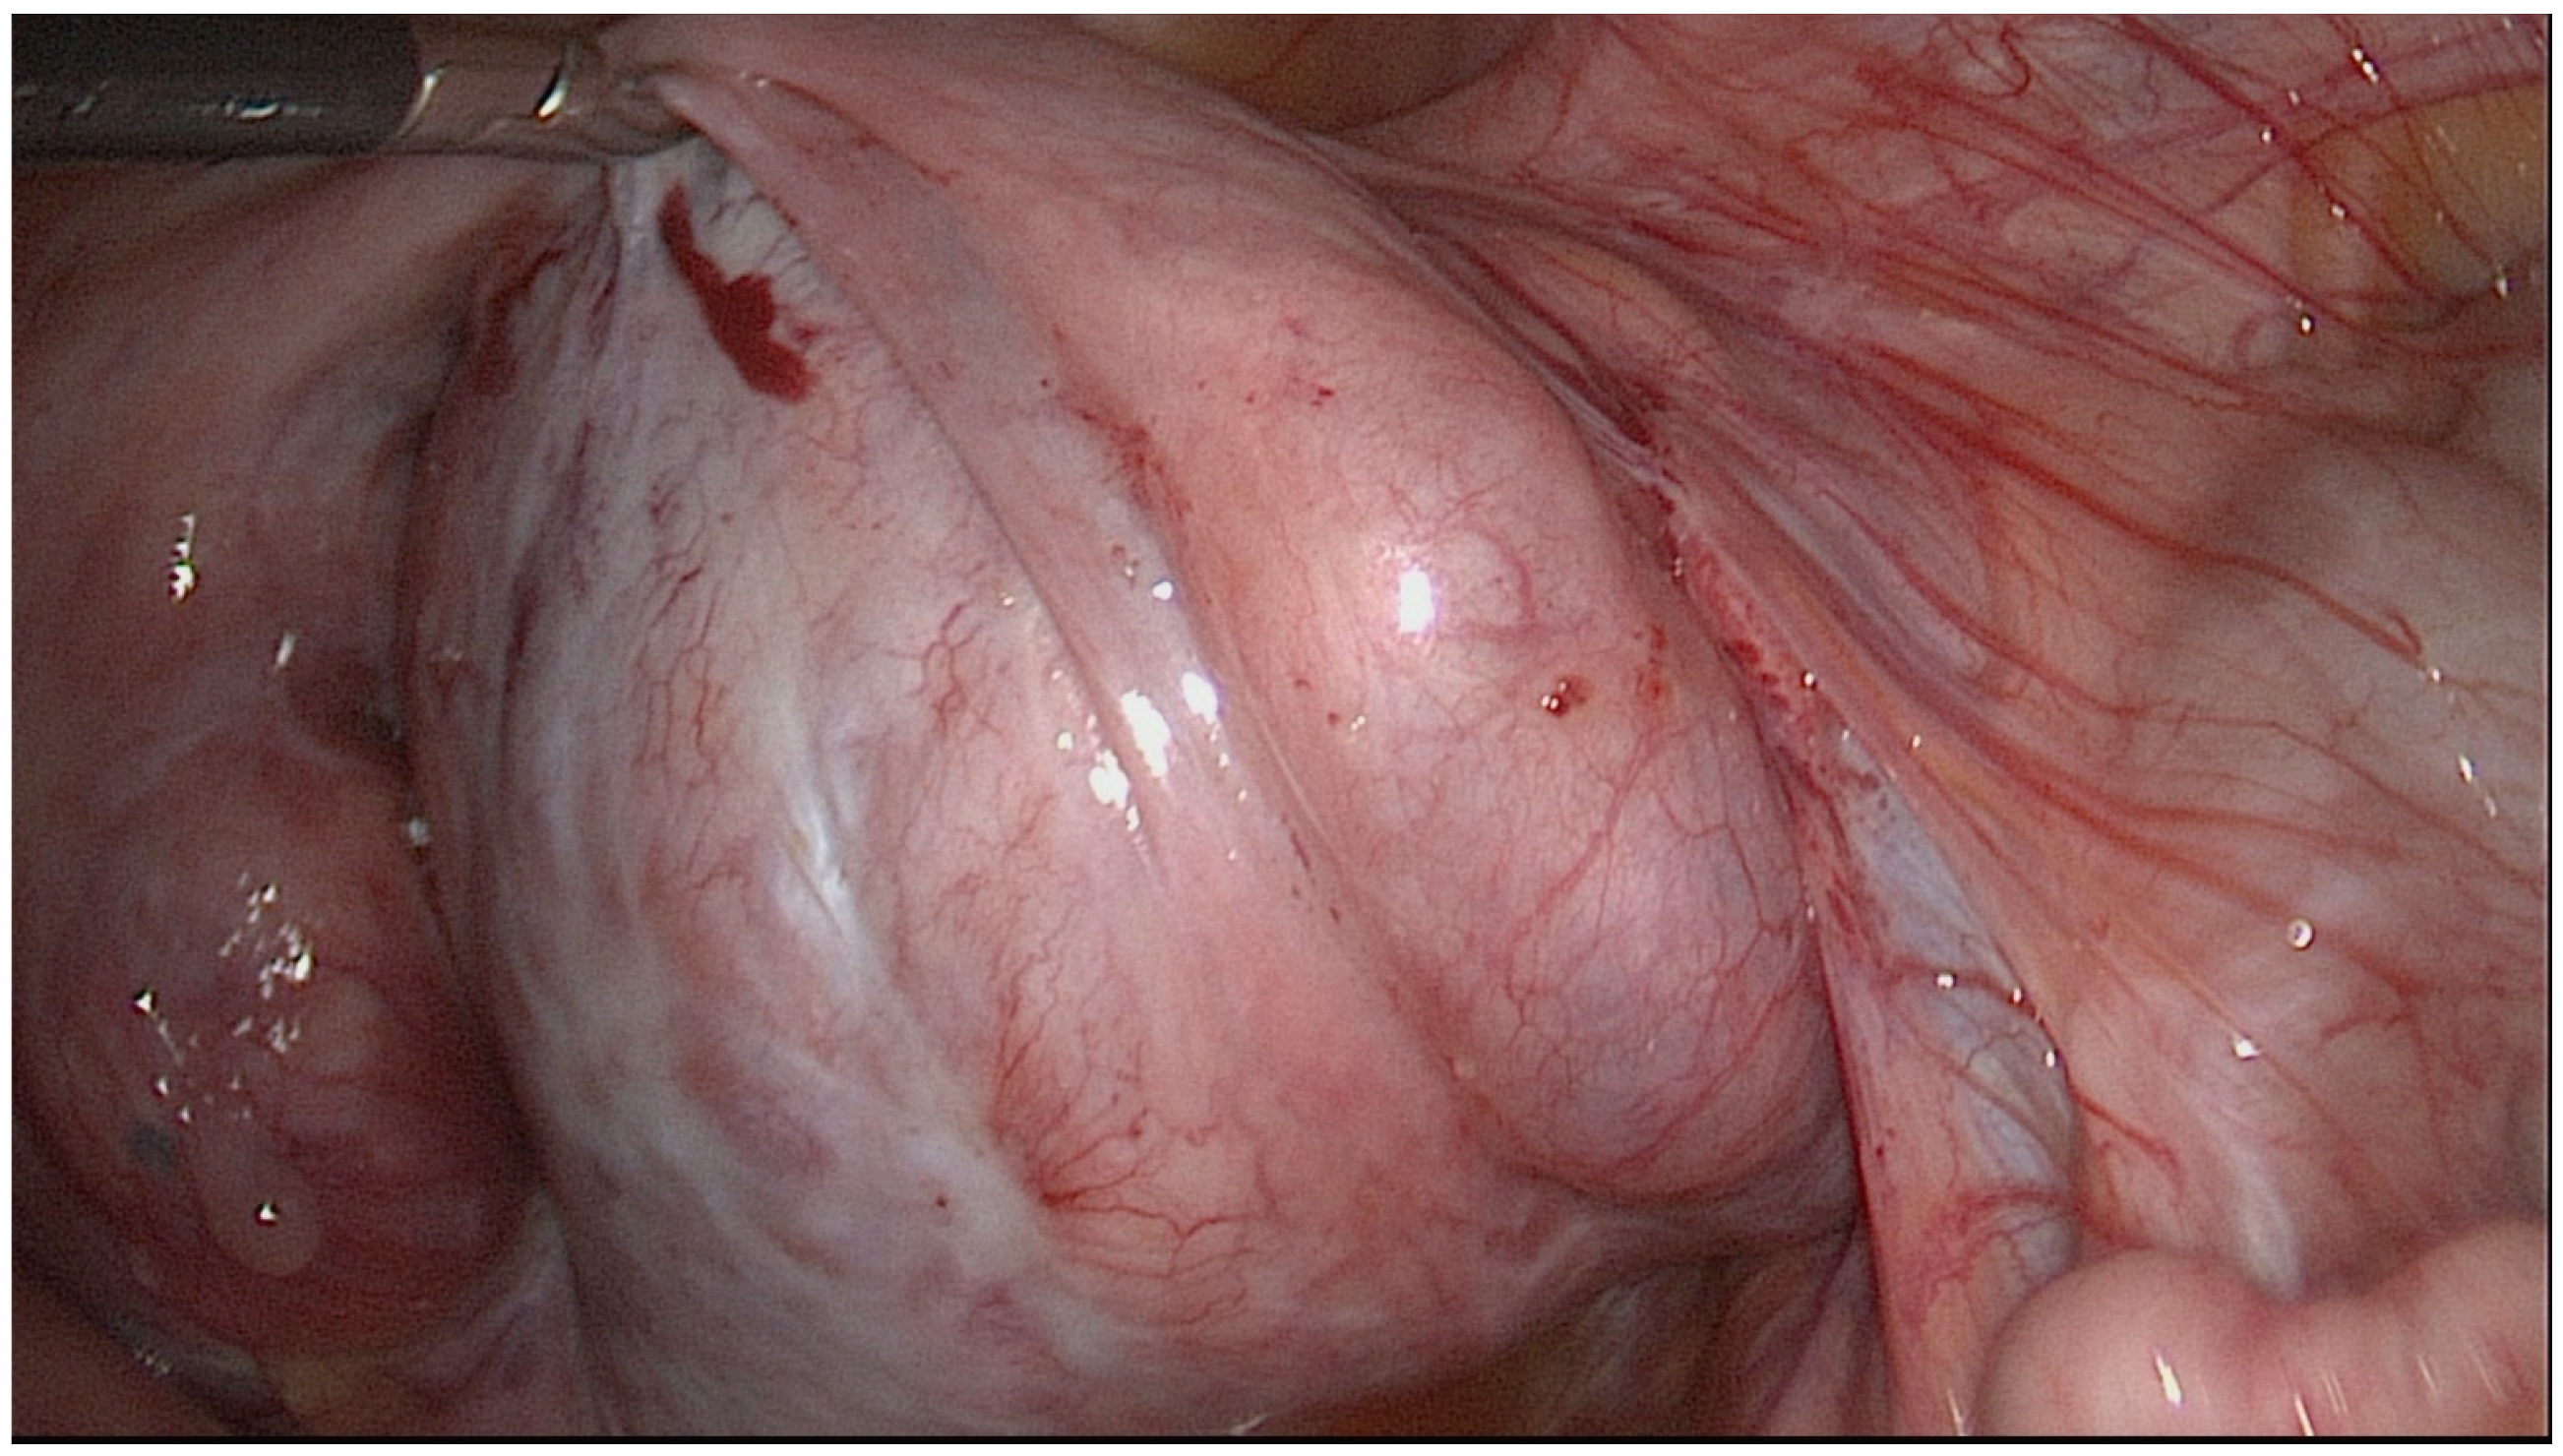

3. Treatment Strategy and Decision-Making Process

4. Operative Techniques in Reconstructive Distal Tubal Surgery